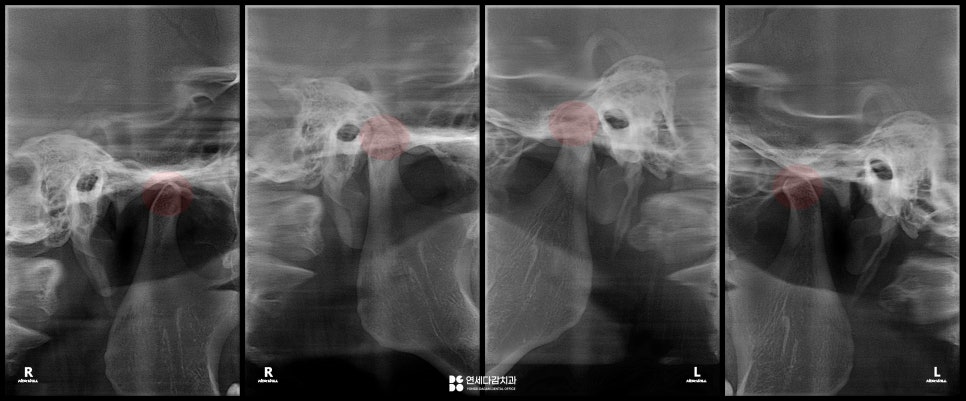

오늘 가락동 치과 에서 소개해 드릴

케이스의 상태를 살펴봤을 때,

26.01.09

턱이 오른쪽으로 쏠리는

편위(deflection)현상이 있습니다.

안면 골격의 비대칭도 일부 발견되지만,

큰 문제가 되는 수준은 아닌 것으로 평가됩니다.